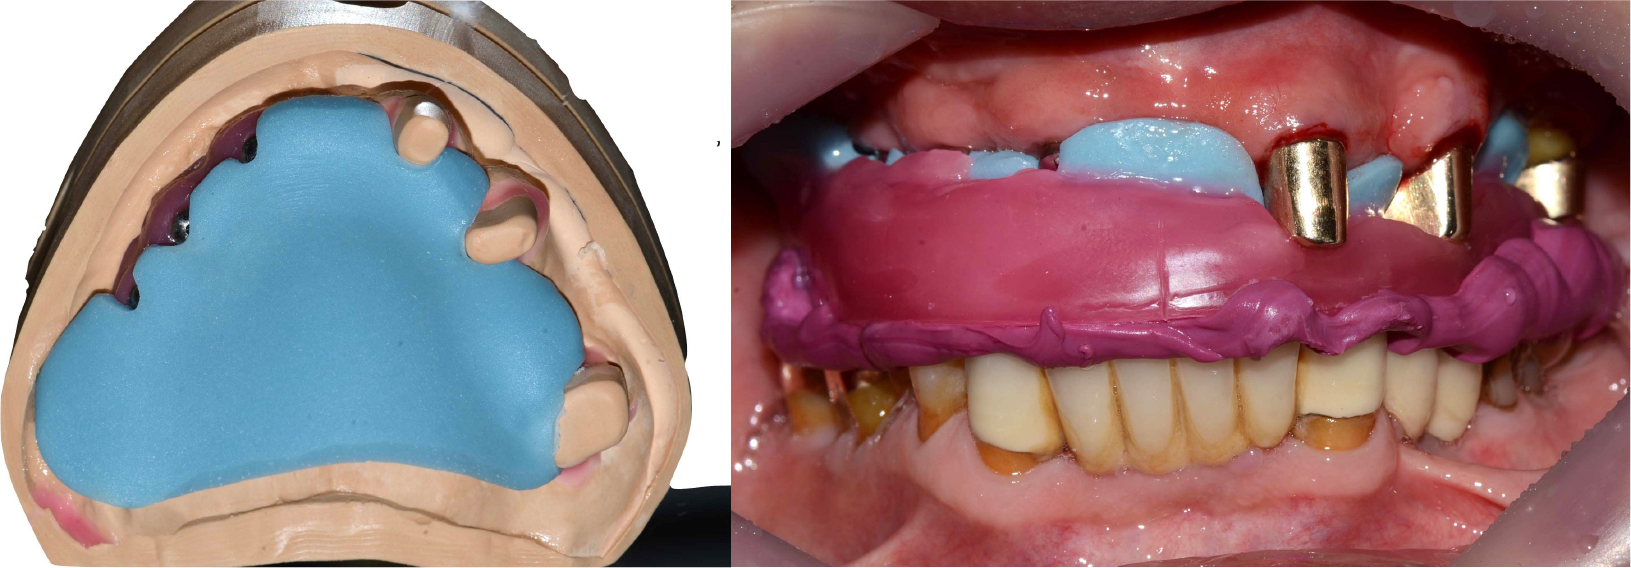

Three months later, after confirmation of implant osseointegration, prosthetic treatment was initiated. A polyether impression (Aquasil Ultra LV; Dentsply, Milford, DE, USA) of the maxillary implants and original teeth with the gold inner crowns was made using a custom tray. The impression was poured using type IV dental gypsum (GC Fujirock EP; GC Europe NV, Leuven, Belgium).

A recording base was fabricated on the master cast for vertical dimension determination and centric relation records. The occlusal rim was adjusted intraorally, and a centric record was prepared using a bite registration material (Cresil bite; Creden, Daegu, Korea) (Fig. 5).